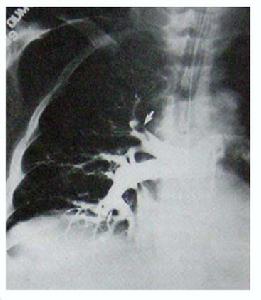

6、肺血管造影,其X線徵象為肺血管內缺損或肺動脈有斷流現象。本方法是診斷肺栓塞最準確而可靠的措施。

5、肺通氣/灌注顯象,肺動脈造影或數字減影血管造影。